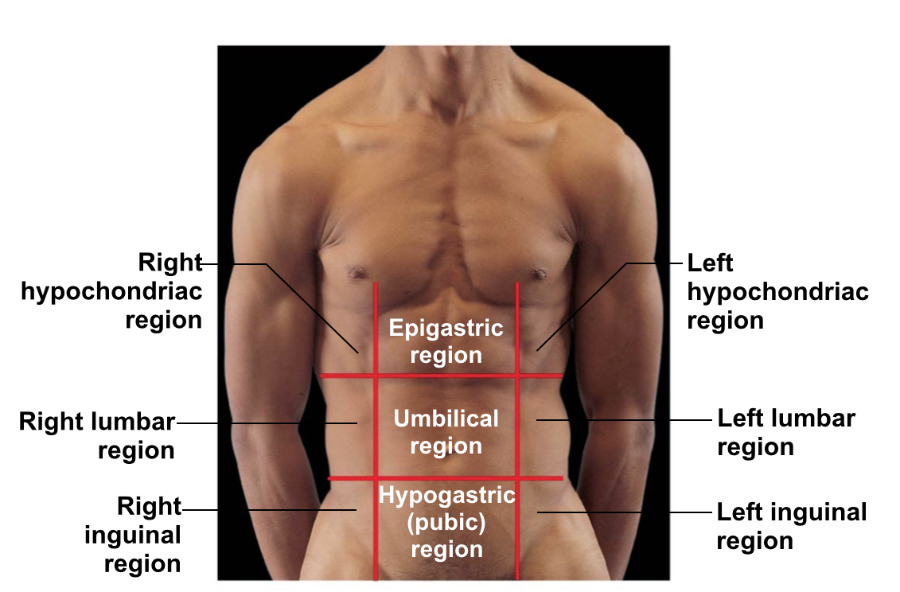

Abdominopelvic regions.

What is 1?

Right hypochondriac region

What is 2?

Right lumbar region

What is 3?

Right inguinal region

What is 4?

Epigastric region

What is 5?

Umbilical region

What is 6?

Hypogastric (pubic) region

The _____________ is in the Left Hypochondriac region

Speen

The ______________ & ______________ are in the Epigastric region

Liver, stomach

The ______________ is in the Hypogastric region.

Urinary Bladder